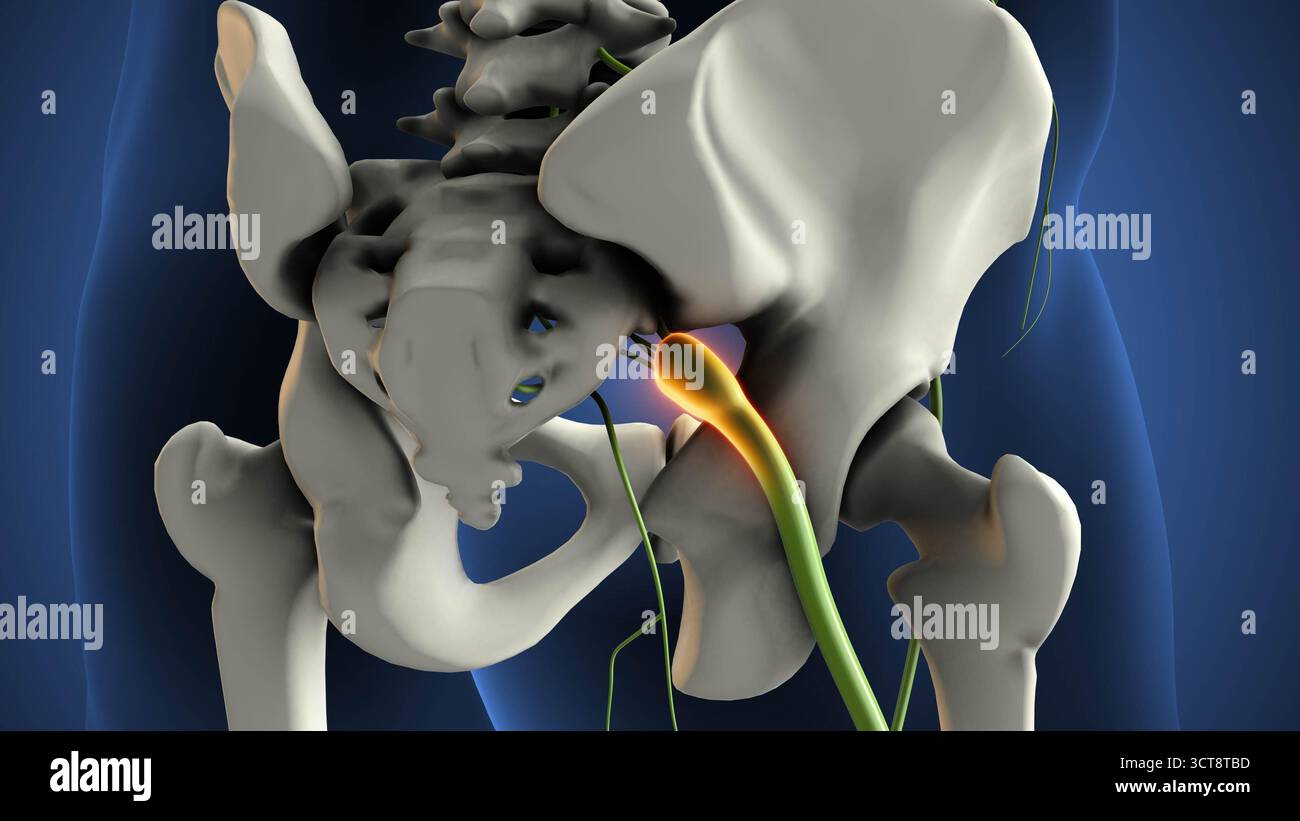

Schwannome droit du nerf sciatique Banque D'Imageshttps://www.alamyimages.fr/image-license-details/?v=1https://www.alamyimages.fr/schwannome-droit-du-nerf-sciatique-image703361217.html

Schwannome droit du nerf sciatique Banque D'Imageshttps://www.alamyimages.fr/image-license-details/?v=1https://www.alamyimages.fr/schwannome-droit-du-nerf-sciatique-image703361217.htmlRF3CT8TBD–Schwannome droit du nerf sciatique